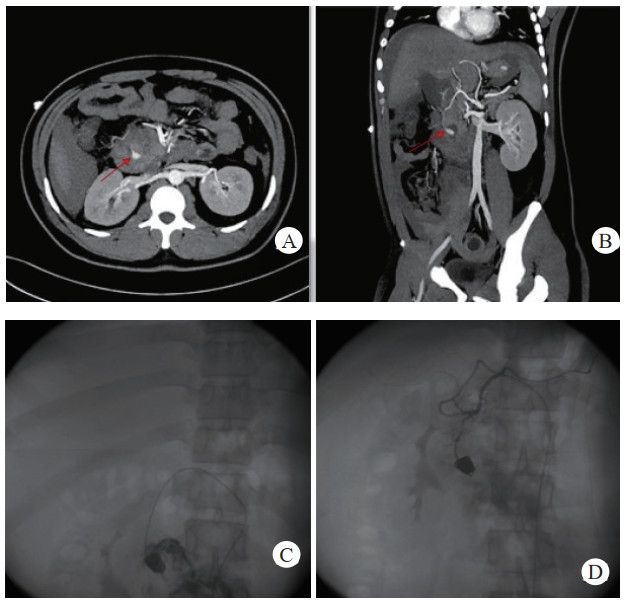

介入栓塞成功率为100%,术中栓塞后即刻复查造影显示,载瘤动脉或假性动脉瘤瘤腔不复显影及未见对比剂外溢,栓塞成功,见图 1(病例1)。

| 注:A、B为患者术前CT增强扫描,示胰腺炎影像,胰头下方血肿影像,中央可见与血管强化方式相同的动脉瘤影像(箭头示),其供血动脉为胰十二指肠上动脉;C为DSA示对比剂充满瘤腔并见对比剂外溢;D为DSA示介入栓塞术后,弹簧圈填满瘤腔及未见对比剂外溢 图 1 病例1术前、术后CT平扫及增强 |